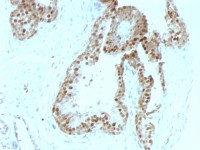

TLR8 antibody

TLR8 抗体

WB analysis of Daudi cell lysate using GTX77620 TLR8 antibody.